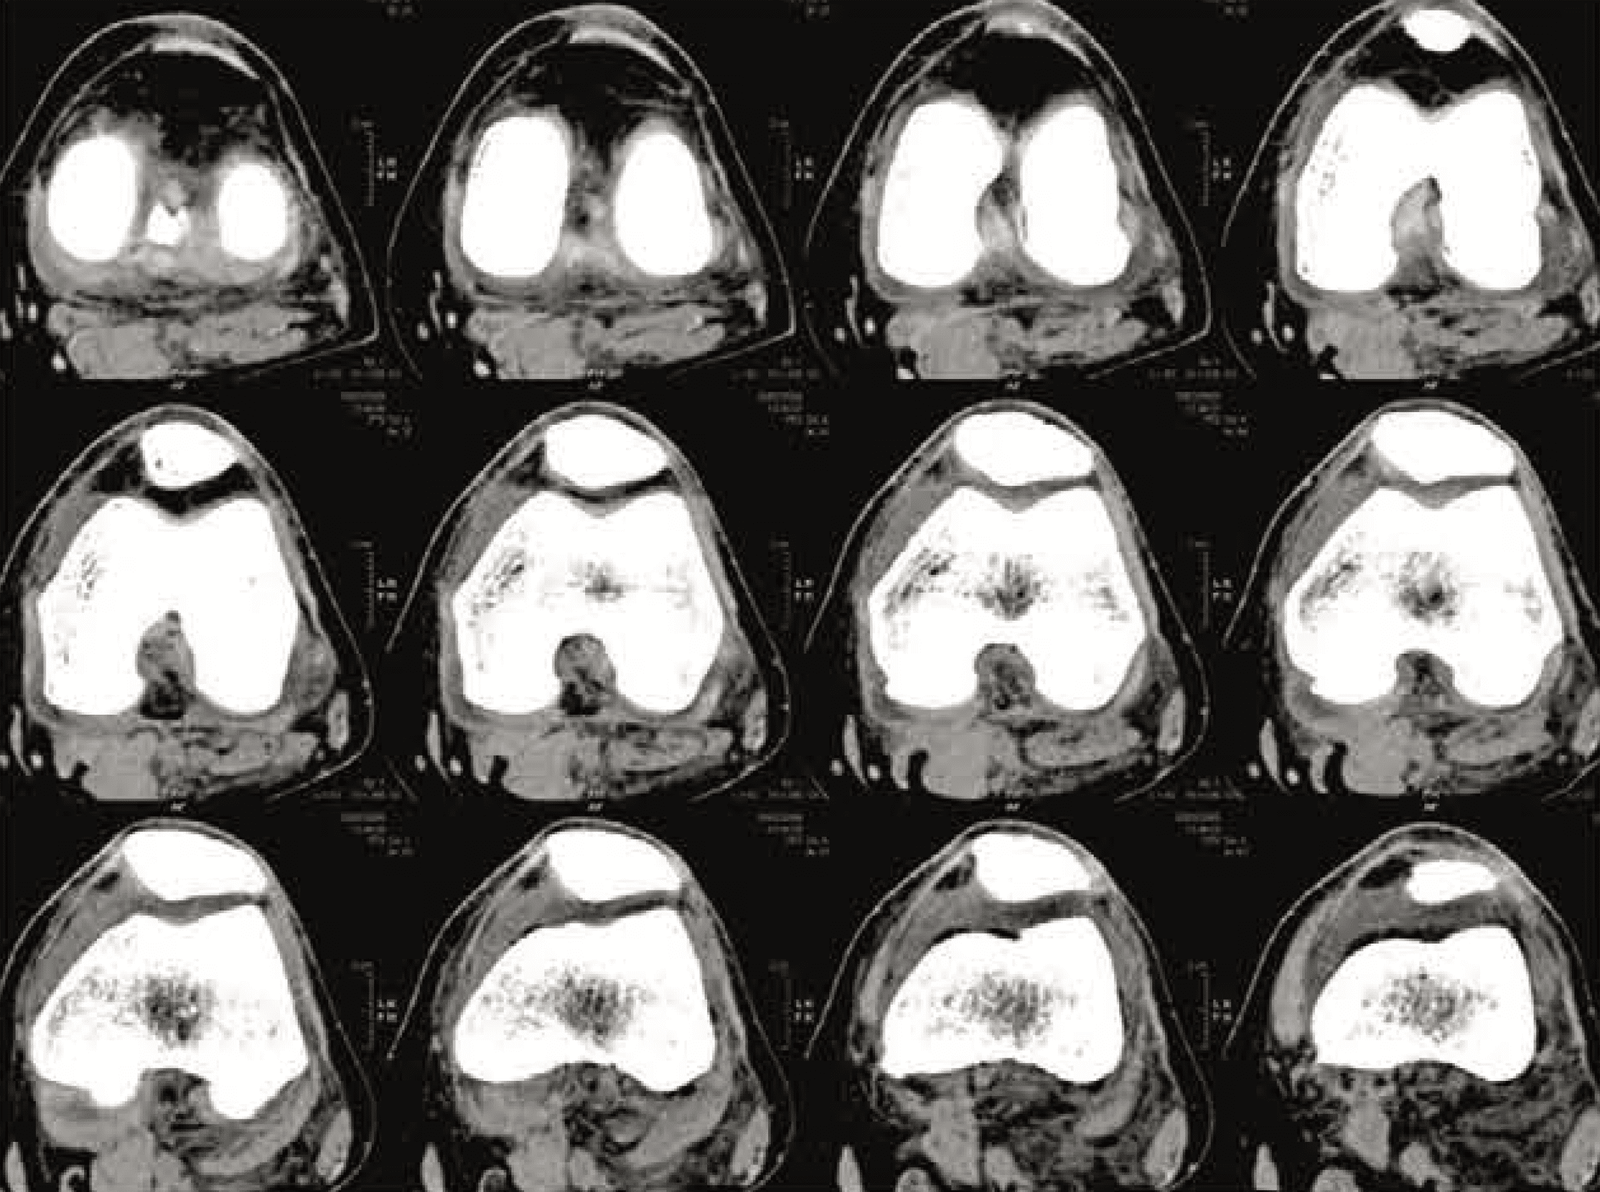

A CT scan of your knee joint is the first step in the process, which is utilized to create a 3D virtual representation of your anatomy. The Mako System software loads this virtual model, which is then utilized to generate your unique preoperative plan.